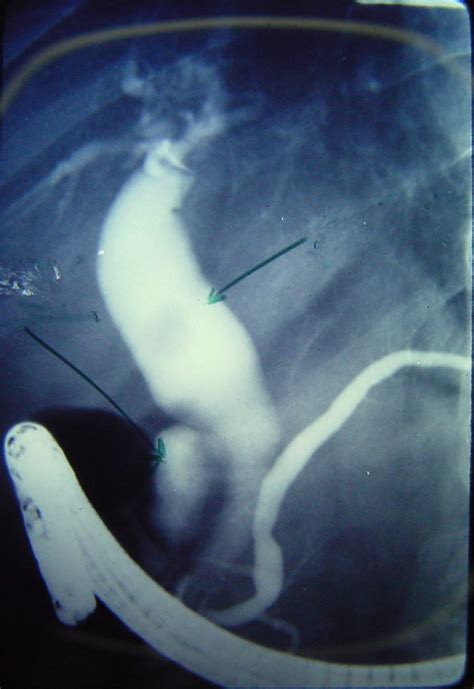

Once bile duct stones are confirmed, the primary goal is to clear the obstruction. The gold standard for treatment is a procedure called Endoscopic Retrograde Cholangiopancreatography (ERCP). During an ERCP, a flexible tube with a camera (endoscope) is passed down the throat into the stomach and the beginning of the small intestine. The doctor can then locate the bile duct, use specialized tools to widen the opening, and retrieve or crush the stone, allowing the bile to flow freely again.